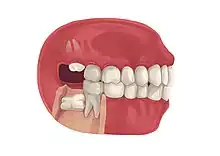

| Types | Full vs partially impacted, direction of impaction |

Impacted wisdom teeth are often described by the direction of their impaction (forward tilting, or mesioangular being the most common), the depth of impaction and the age of the patient as well as other factors such as pre-existing infection or the presence of pathology (cysts, tumors or other disease).[5]: 143–144 Each of these factors is used to predict the difficulty (and rate of complications) when removing an impacted tooth, with age being the most reliable predictor[8] rather than the orientation of the impaction.[9]